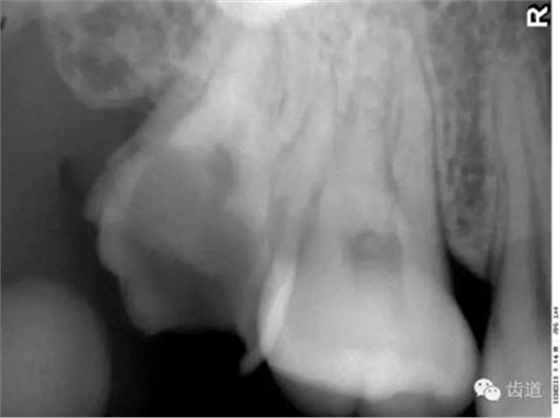

在投照上頜磨牙根尖片時(shí),經(jīng)常可以看到牙根上方有一密度低的影像,為上頜竇的一部分,邊緣環(huán)繞以密度高的線狀影像,為上頜竇壁致密骨層。有時(shí)可見(jiàn)上頜竇的分隔。

可在第一、二磨牙根尖上方或重疊在牙根上為近似三角形或半圓形密度高的影像。

常在上頜第二、三磨牙的牙冠區(qū)域有一較牙密度稍低由后伸向前方的三角形影像。

在最后一個(gè)磨牙遠(yuǎn)中區(qū)域,其邊緣向后上,X線片上常呈稀疏的網(wǎng)狀結(jié)構(gòu),為正常疏松區(qū)。

在上頜結(jié)節(jié)后方,呈長(zhǎng)條狀邊緣整齊、寬約0.2cm、長(zhǎng)約1cm、直的或下端略向后方彎曲的密度稍高的影像。

在第一磨牙腭側(cè)根上方呈圓形密度低影像。